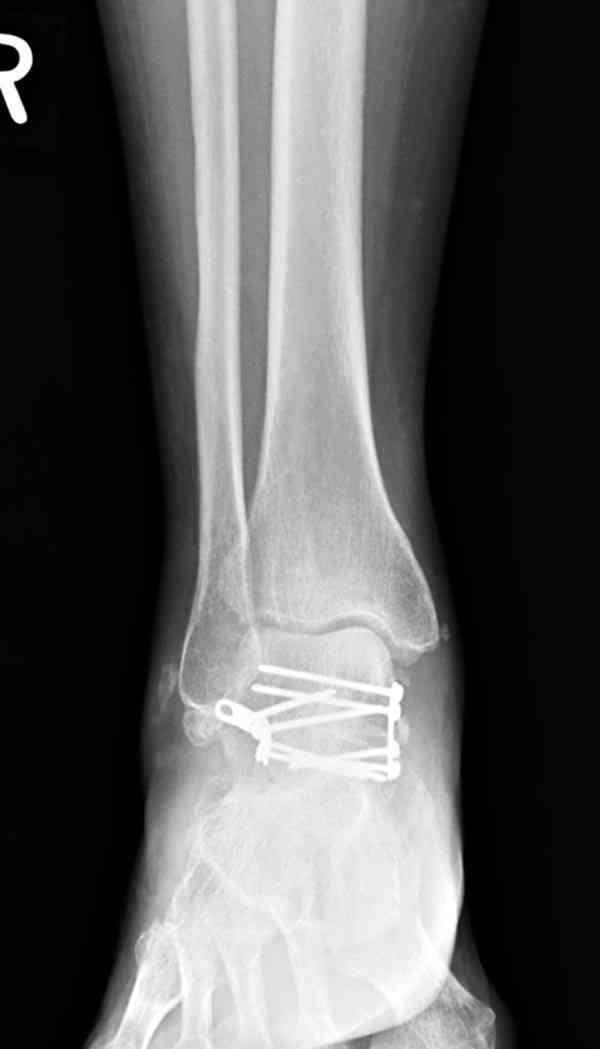

Случай с множественным оскольчатым переломом тарана оперированный из двойного доступа.

Через 2 мес.: